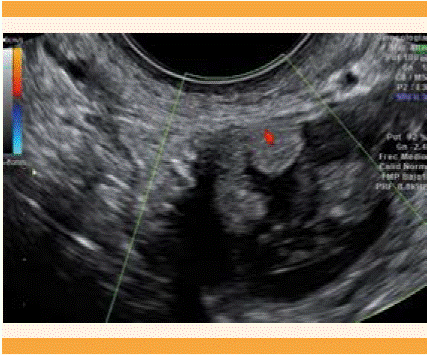

Paciente de 38 años, con hallazgo ecográfico de una formación anexial sospechosa de malignidad en una revisión ginecológica previa a un nuevo ciclo de estimulación ovárica. Un examinador experto observó una formación quística de 25 x 33 mm, de pared gruesa e irregular, con papila de 6 mm, vascularizada; el resto del contenido quístico era heterogéneo (Figuras 1, 2). El ovario izquierdo se observó normal, de 19 x 10 mm. En el útero, el endometrio era homogéneo y congruente con la fase del ciclo. El cuerpo uterino tenía un mioma de 10 x 13 mm, en la cara posterior. No se visualizó líquido libre.